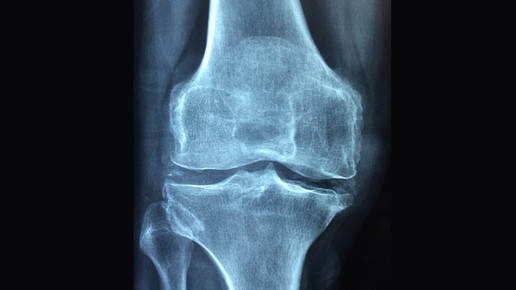

Israelische Forscher haben einem Patienten im Labor gezüchtetes Knochengewebe aus körpereigenen Zellen implantiert. Damit sei eine Lücke von vier Zentimetern in seinem Schienbein geschlossen worden, sagte Nimrod Rozen, der behandelnde Arzt vom Haemek Krankenhaus im Norden Israels. Der Patient sei einer von insgesamt drei Menschen, bei denen das Verfahren als Teil einer klinischen Studie im vergangenen halben Jahr angewendet wurde.

Der 44-Jährige hatte sich bei einem Fahrradunfall das Schienbein gebrochen. Trotz einer Operation, bei der ihm ein Nagel eingesetzt worden war, wuchs der Knochen nicht wieder zusammen, berichtete Rozen. Er leitet die Abteilung für Orthopädie und Rehabilitation der Klinik.

Innerhalb von zwei Wochen wird so im Labor Knochengewebe gezüchtet. Das Gewebe wird mit einer Spritze an die betroffene Körperstelle injiziert. Die Ärzte legen die umliegenden Muskeln um das neue Knochengewebe, um dieses zu stabilisieren. Innerhalb von zwei Monaten entwickle sich das Gewebe zu einem Knochen und verbinde sich mit den angrenzenden Knochenstücken, sagt Meretzki. Nach insgesamt vier bis sechs Monaten habe das neue Knochenstück auch Mark. Der neue Knochen verhalte sich ganz normal, bei Jugendlichen etwa wachse er mit. „Weil jeder Patient einen Knochen bekommt, der aus seinen eigenen Zellen geschaffen wurde, gibt es keine Nebenwirkungen, es besteht nicht die Gefahr einer Immunabwehr“, erklärt Meretzki.

Mehr als zehn Zentimeter ist das von den Wissenschaftlern größte gezüchtete Knochenstück lang, allerdings nur zu Forschungszwecken. Mediziner Rozen sagt, dass Knochenlücken von maximal fünf Zentimetern geschlossen werden könnten, mehr würden Muskeln und Nerven nicht erlauben.

Die israelischen Wissenschaftler betonen allerdings, dass Menschen vor allem durch den Alterungsprozess, Infektionen oder Tumore Knochen verlören. So könnten mit dem Verfahren auch etwa durch Osteoporose brüchige Knochen wieder gefestigt werden, sagt Rozen.